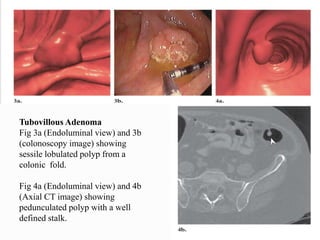

This document discusses colorectal polyps. It defines polyps and describes their types, including neoplastic and non-neoplastic polyps. It discusses adenomatous polyps in depth, noting their malignant potential increases with size over 1cm and villous architecture. Radiological diagnostic methods for polyps including single and double contrast barium enema and CT colonography are explained. The document provides an overview of polyp pathogenesis and genetic syndromes like FAP that increase cancer risk.